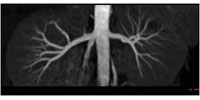

腎動脈非造影MRA |